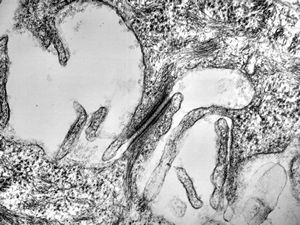

F,76y. | intranuclear needle-like structures - rhabdomyoma,tongue

F,76y. | intranuclear needle-like structures - rhabdomyoma,tongue